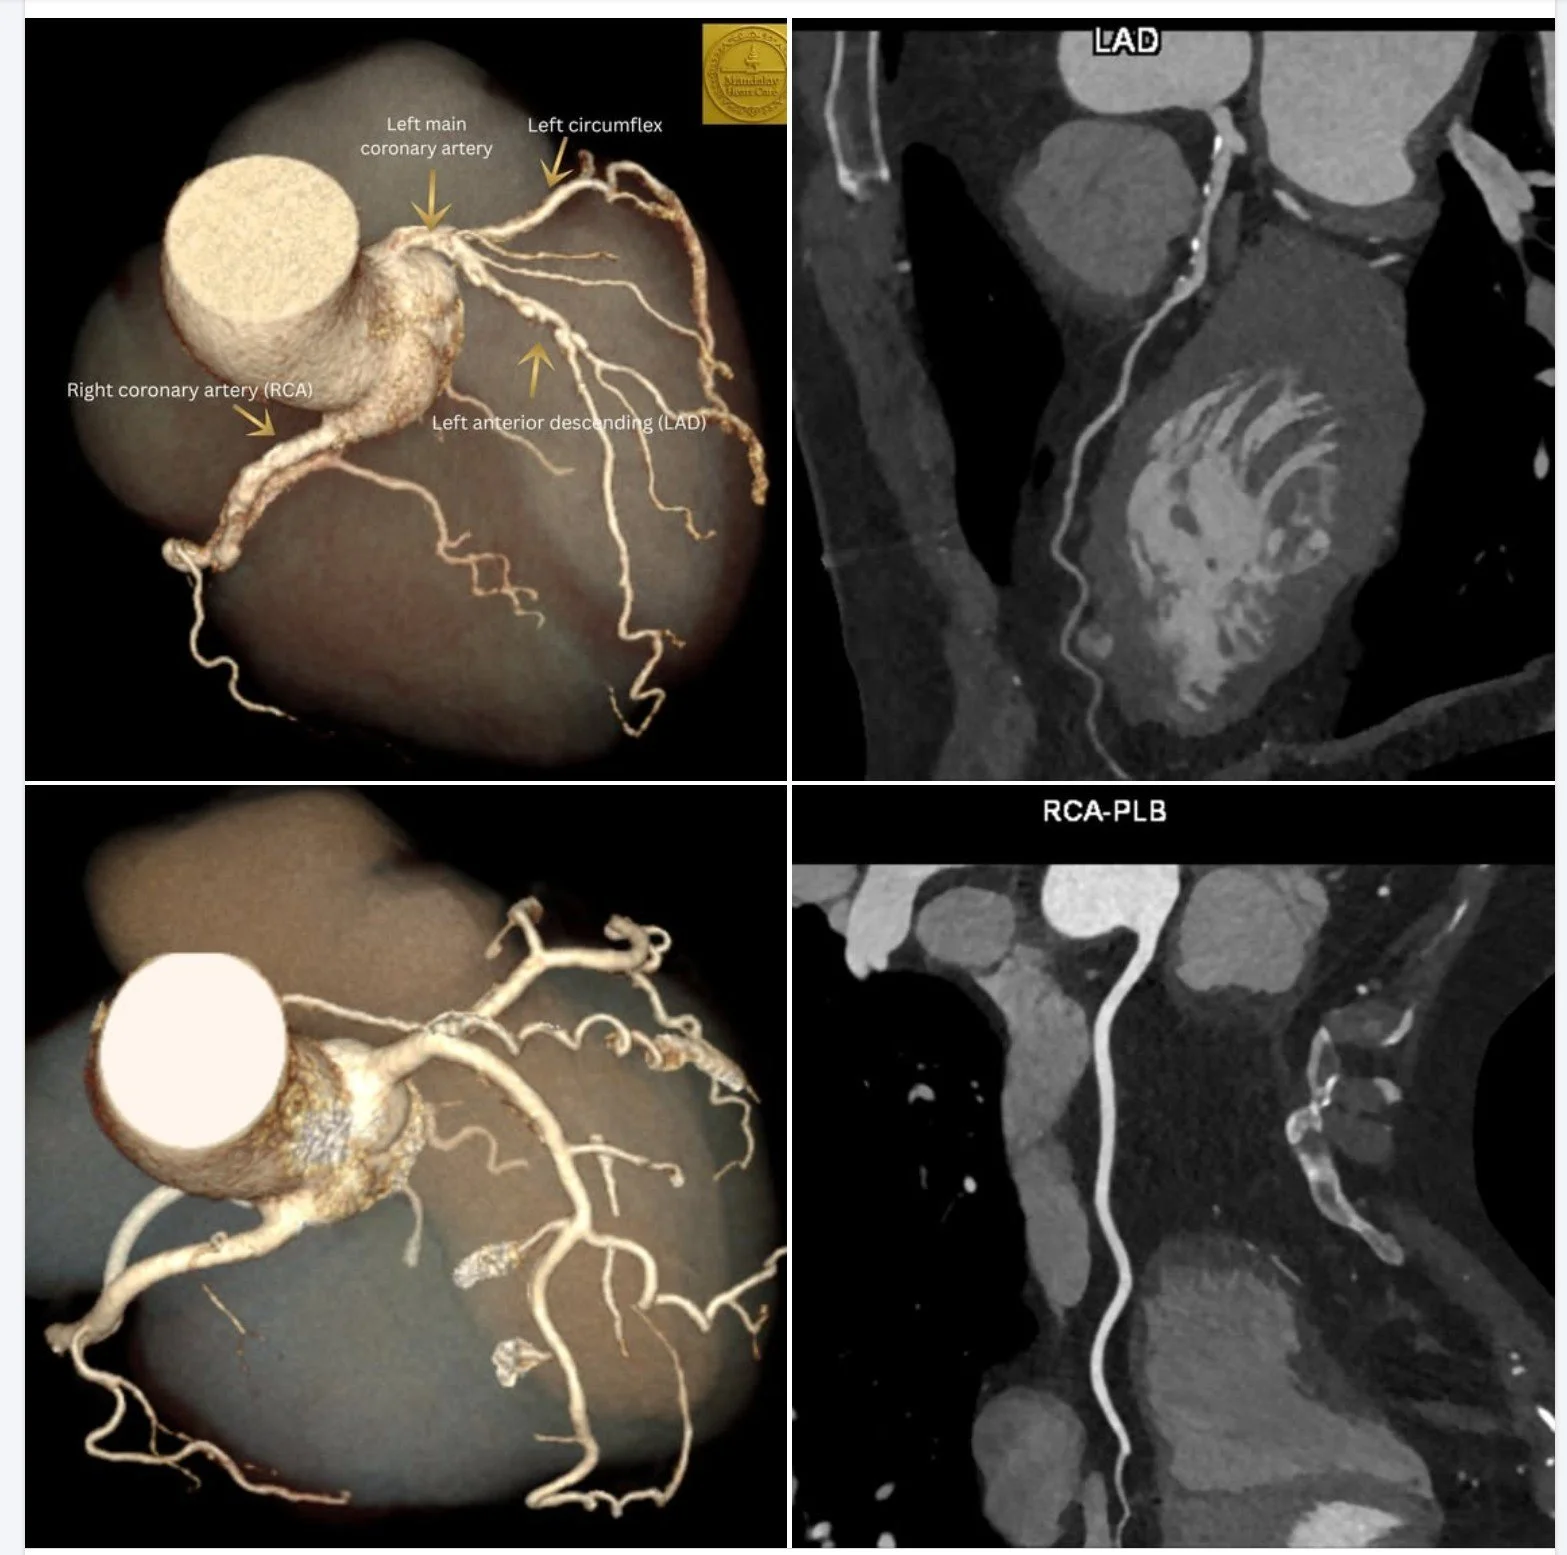

Medical images showing coronary arteries with labels for left main coronary artery, left circumflex, right coronary artery, and left anterior descending artery, including CT scans and 3D reconstructions of the heart's blood vessels.